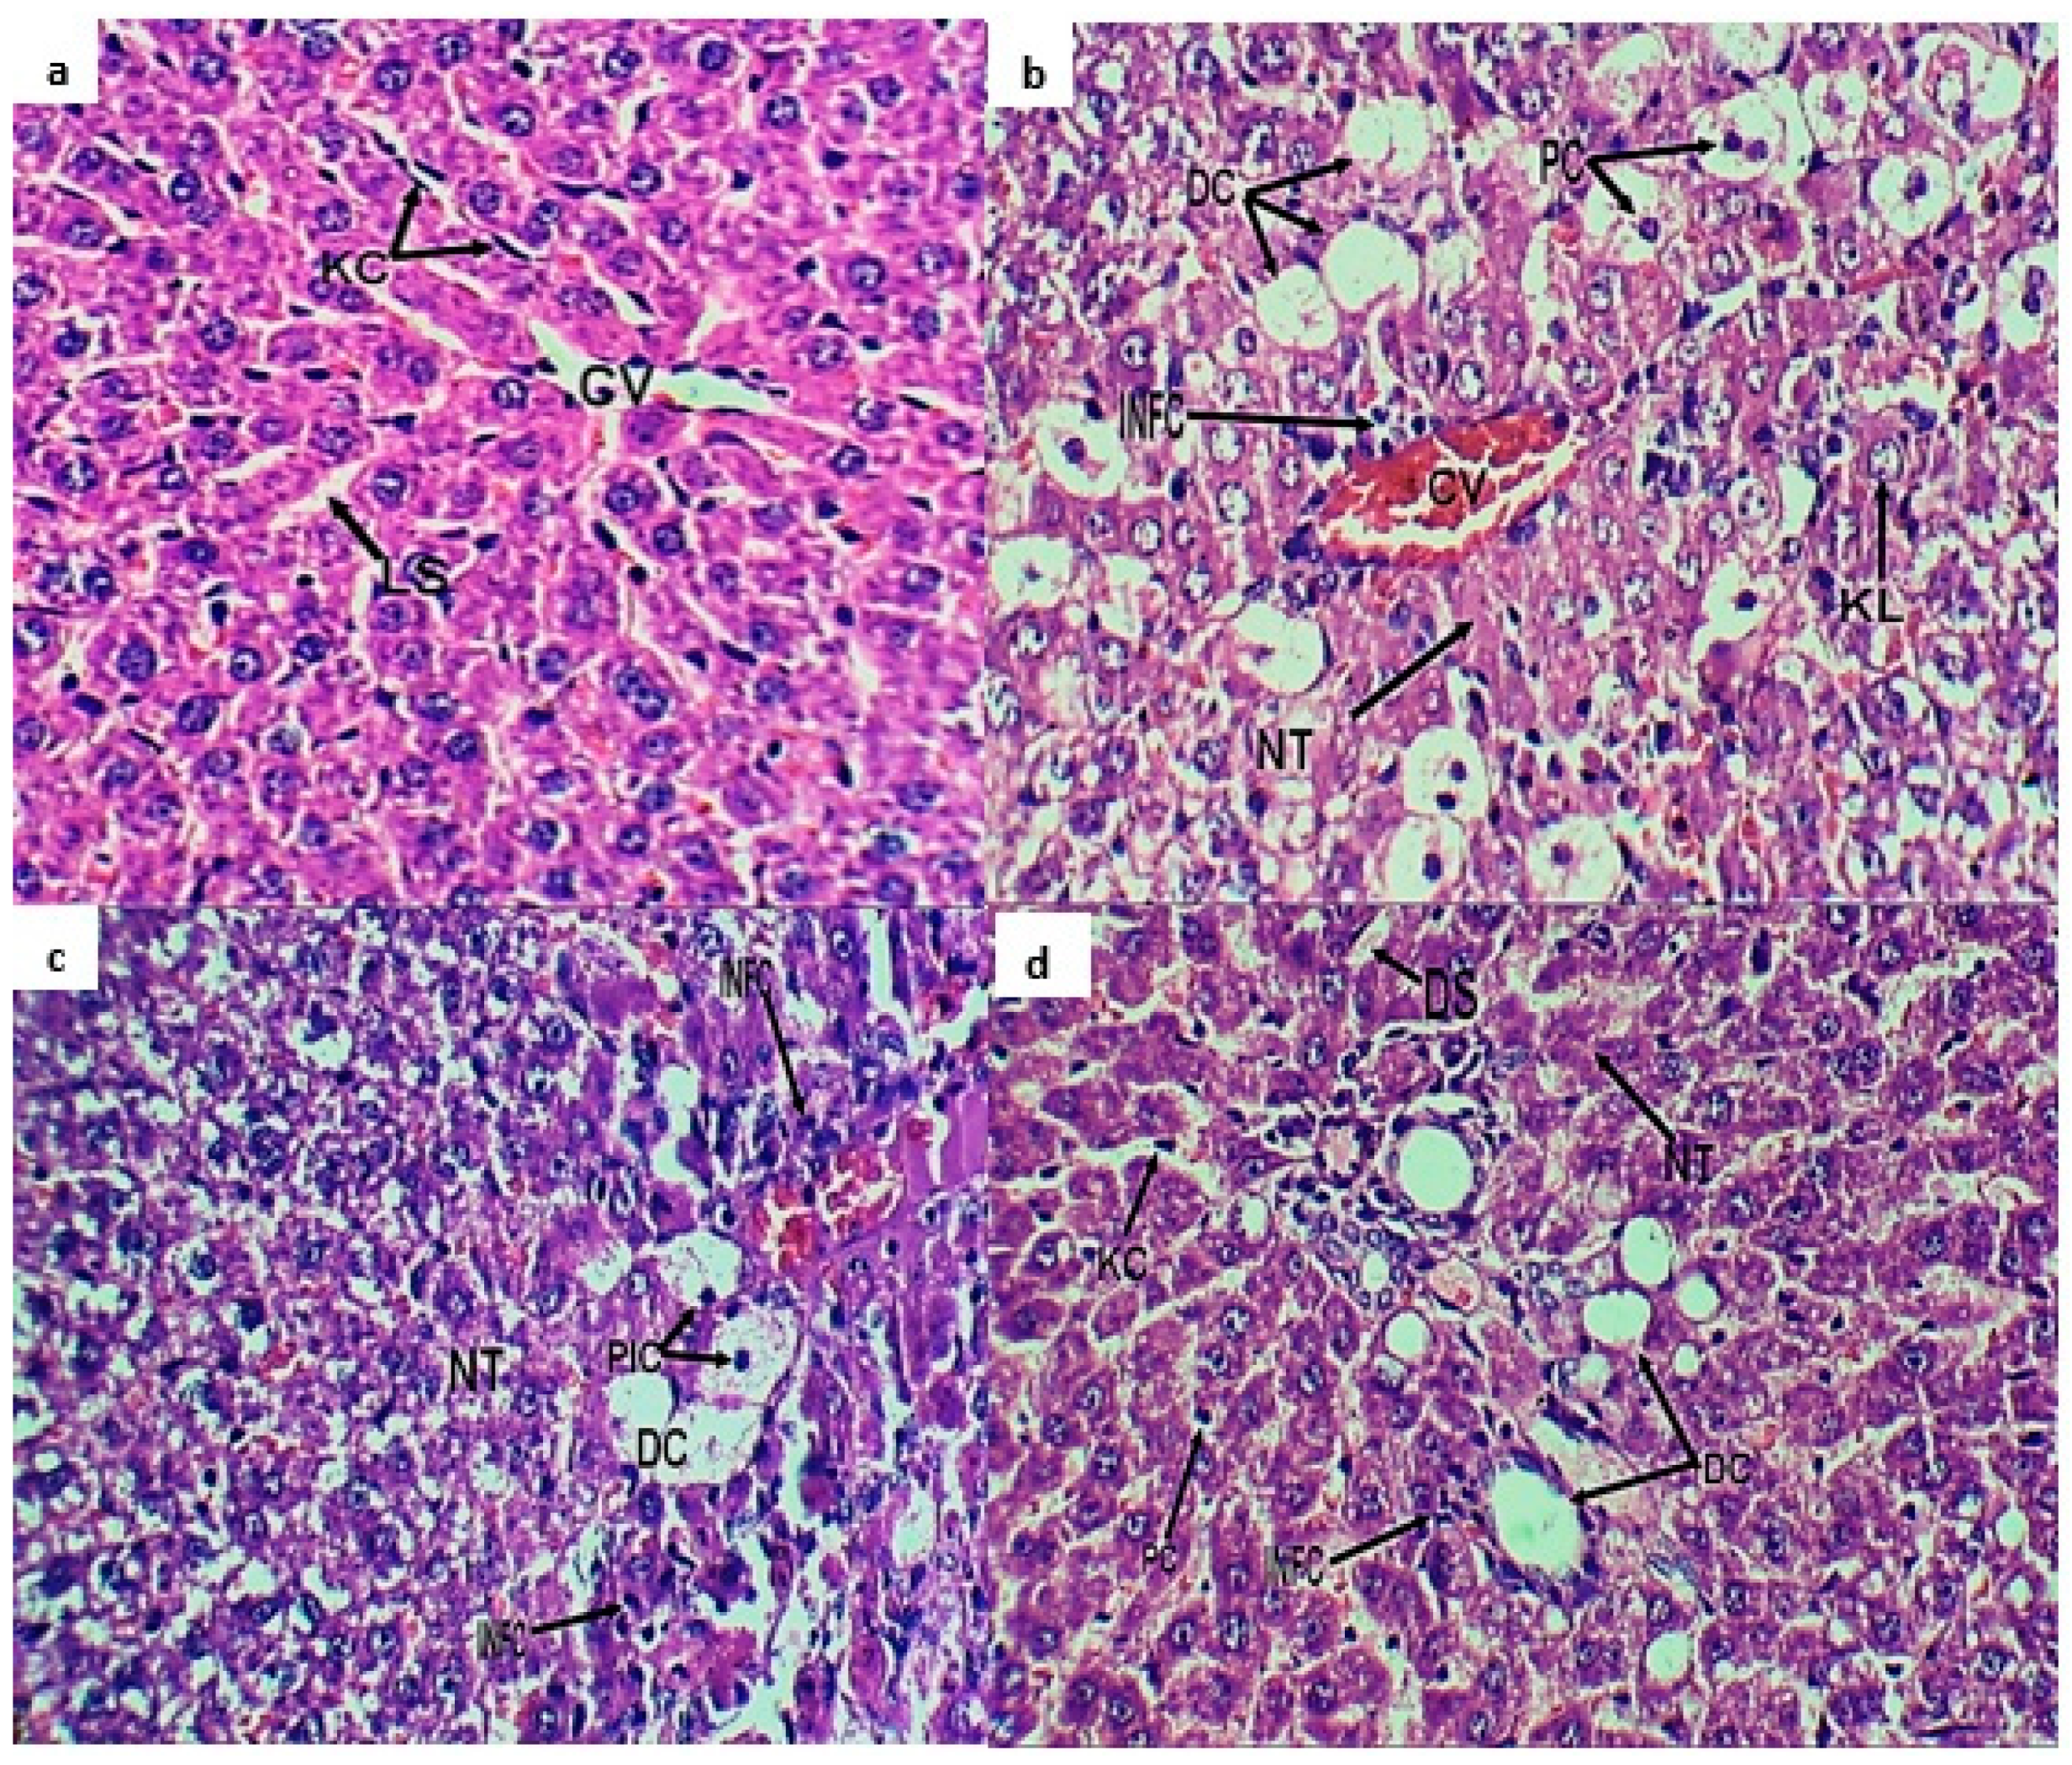

2.3. Histopathological Investigation